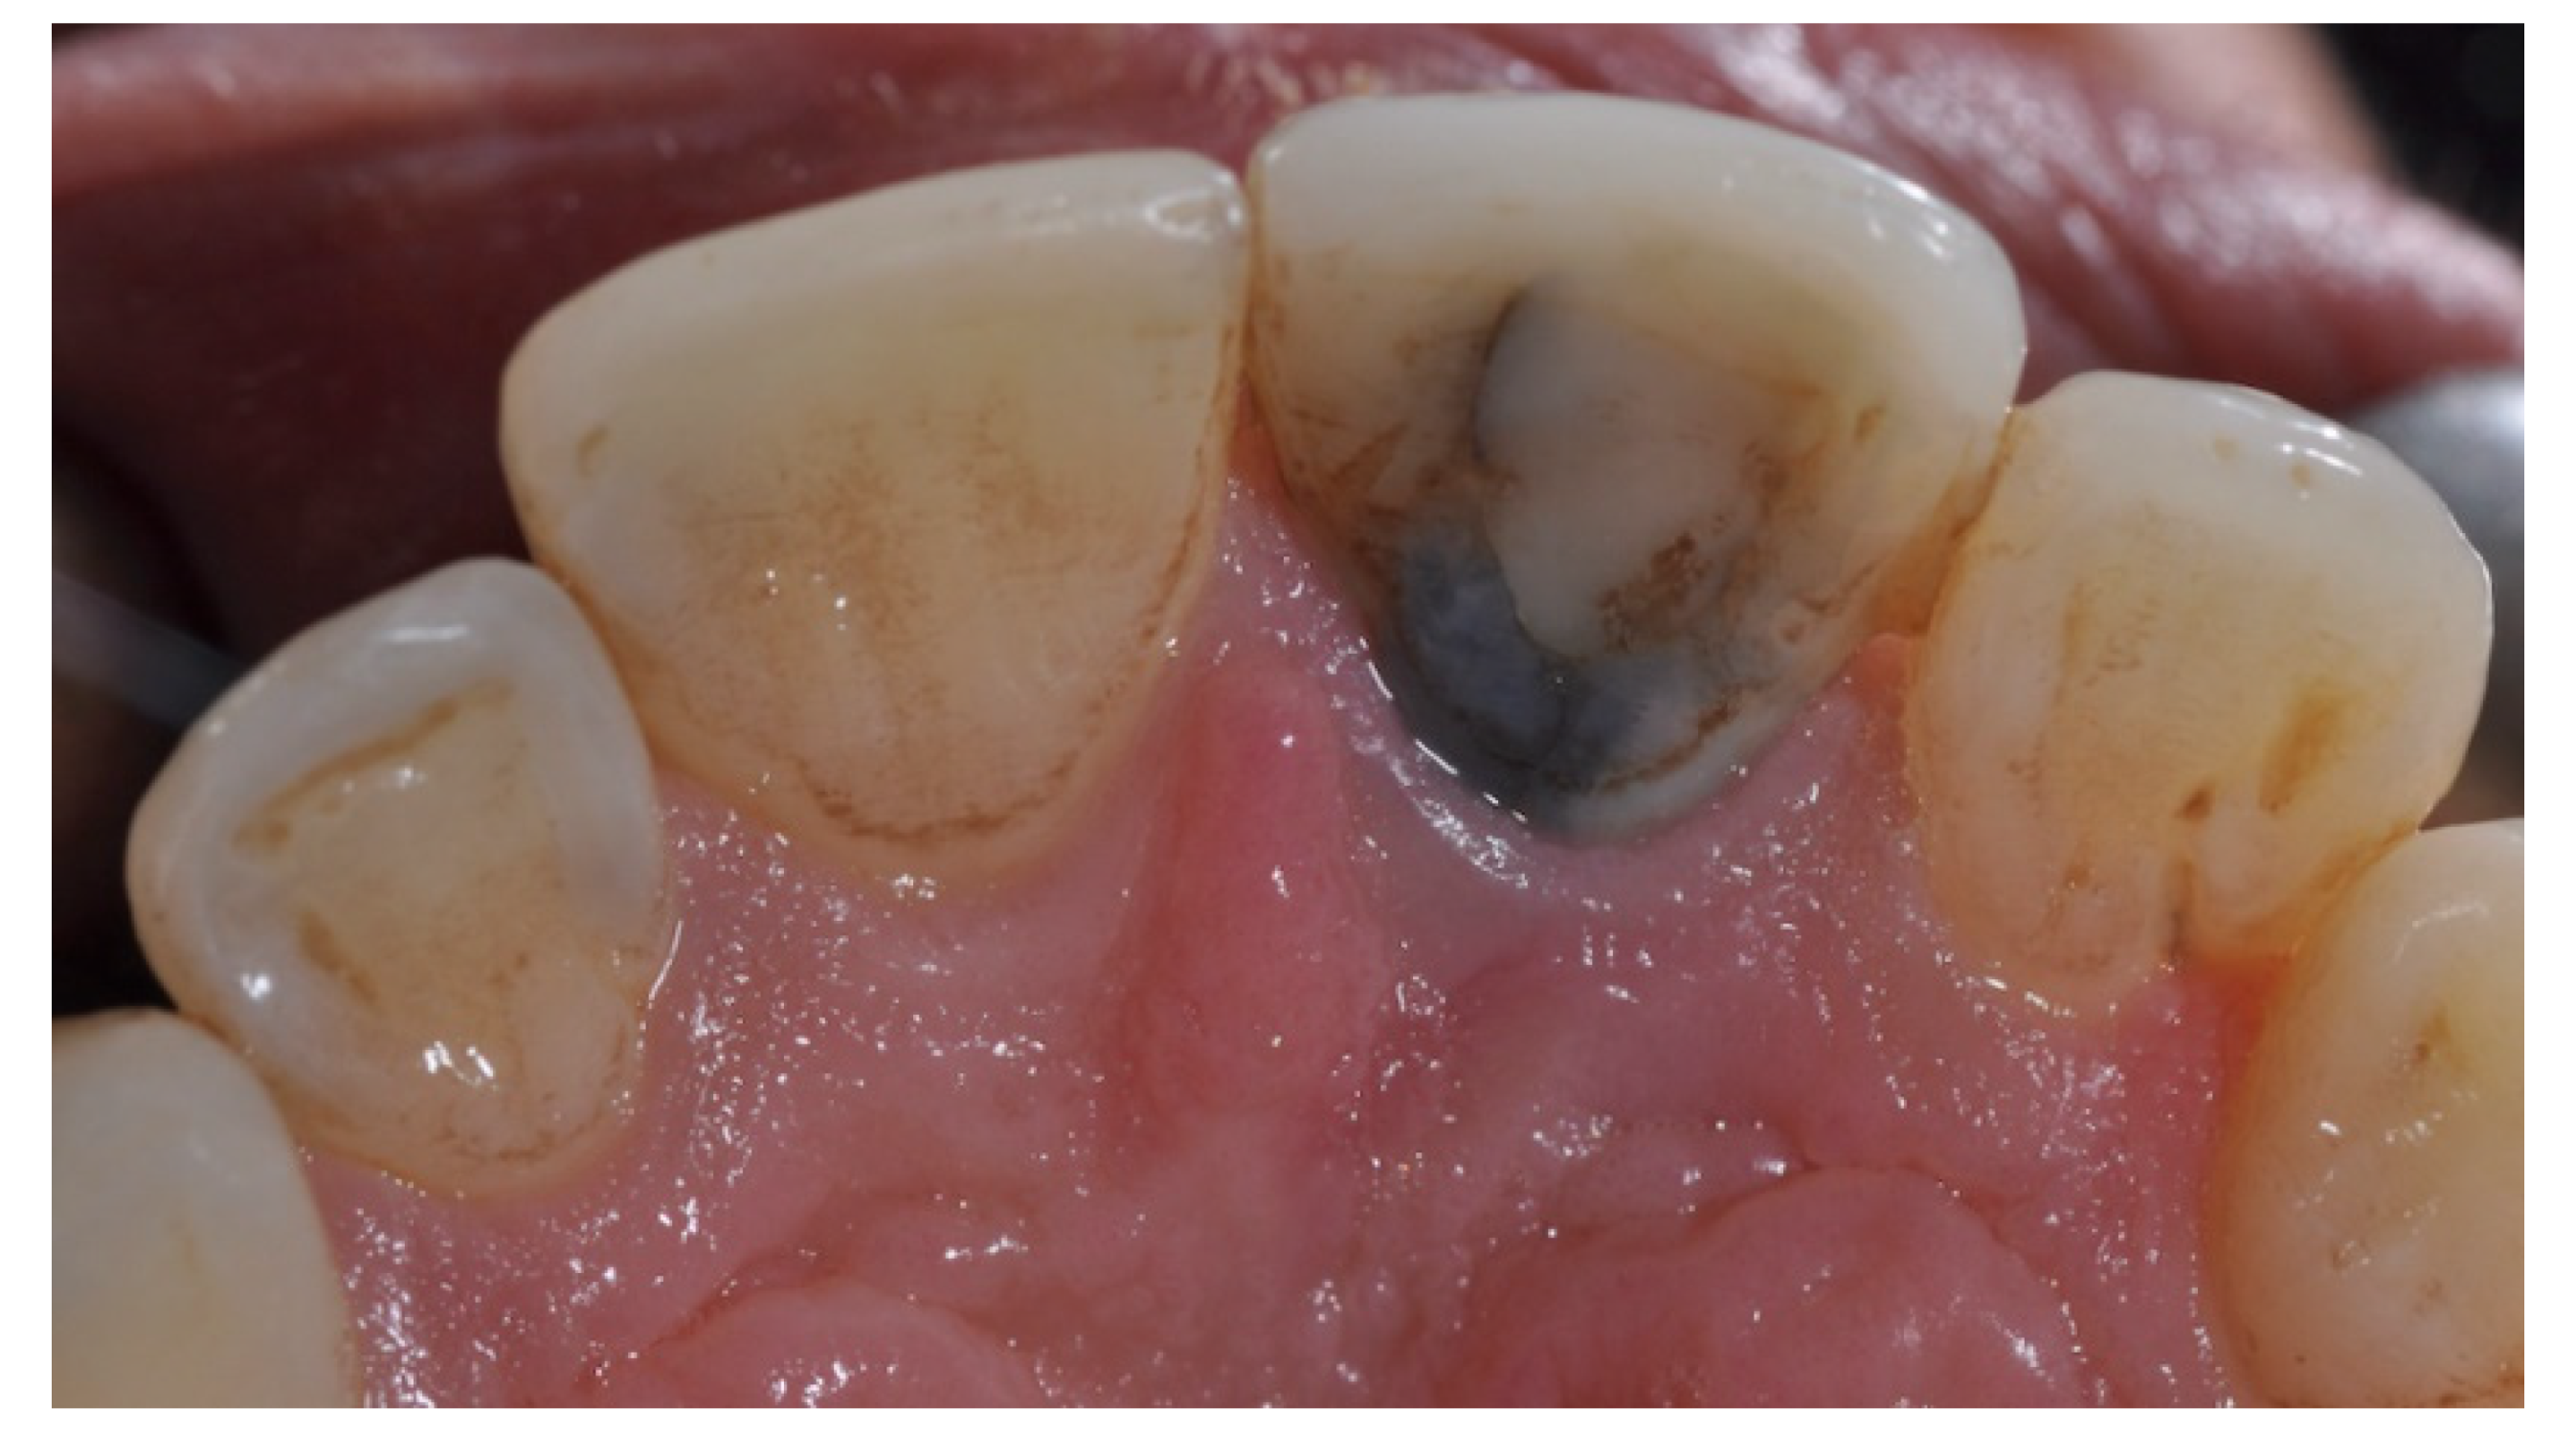

2. Case Presentation